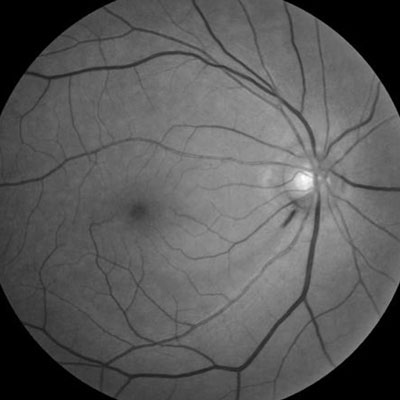

Optic disc hemorrhage is a common clinical feature of glaucoma, indicating active disease with likely progression and visual field loss. Detection necessitates the utmost vigilance in patients diagnosed with glaucoma and in those who are glaucoma suspects.